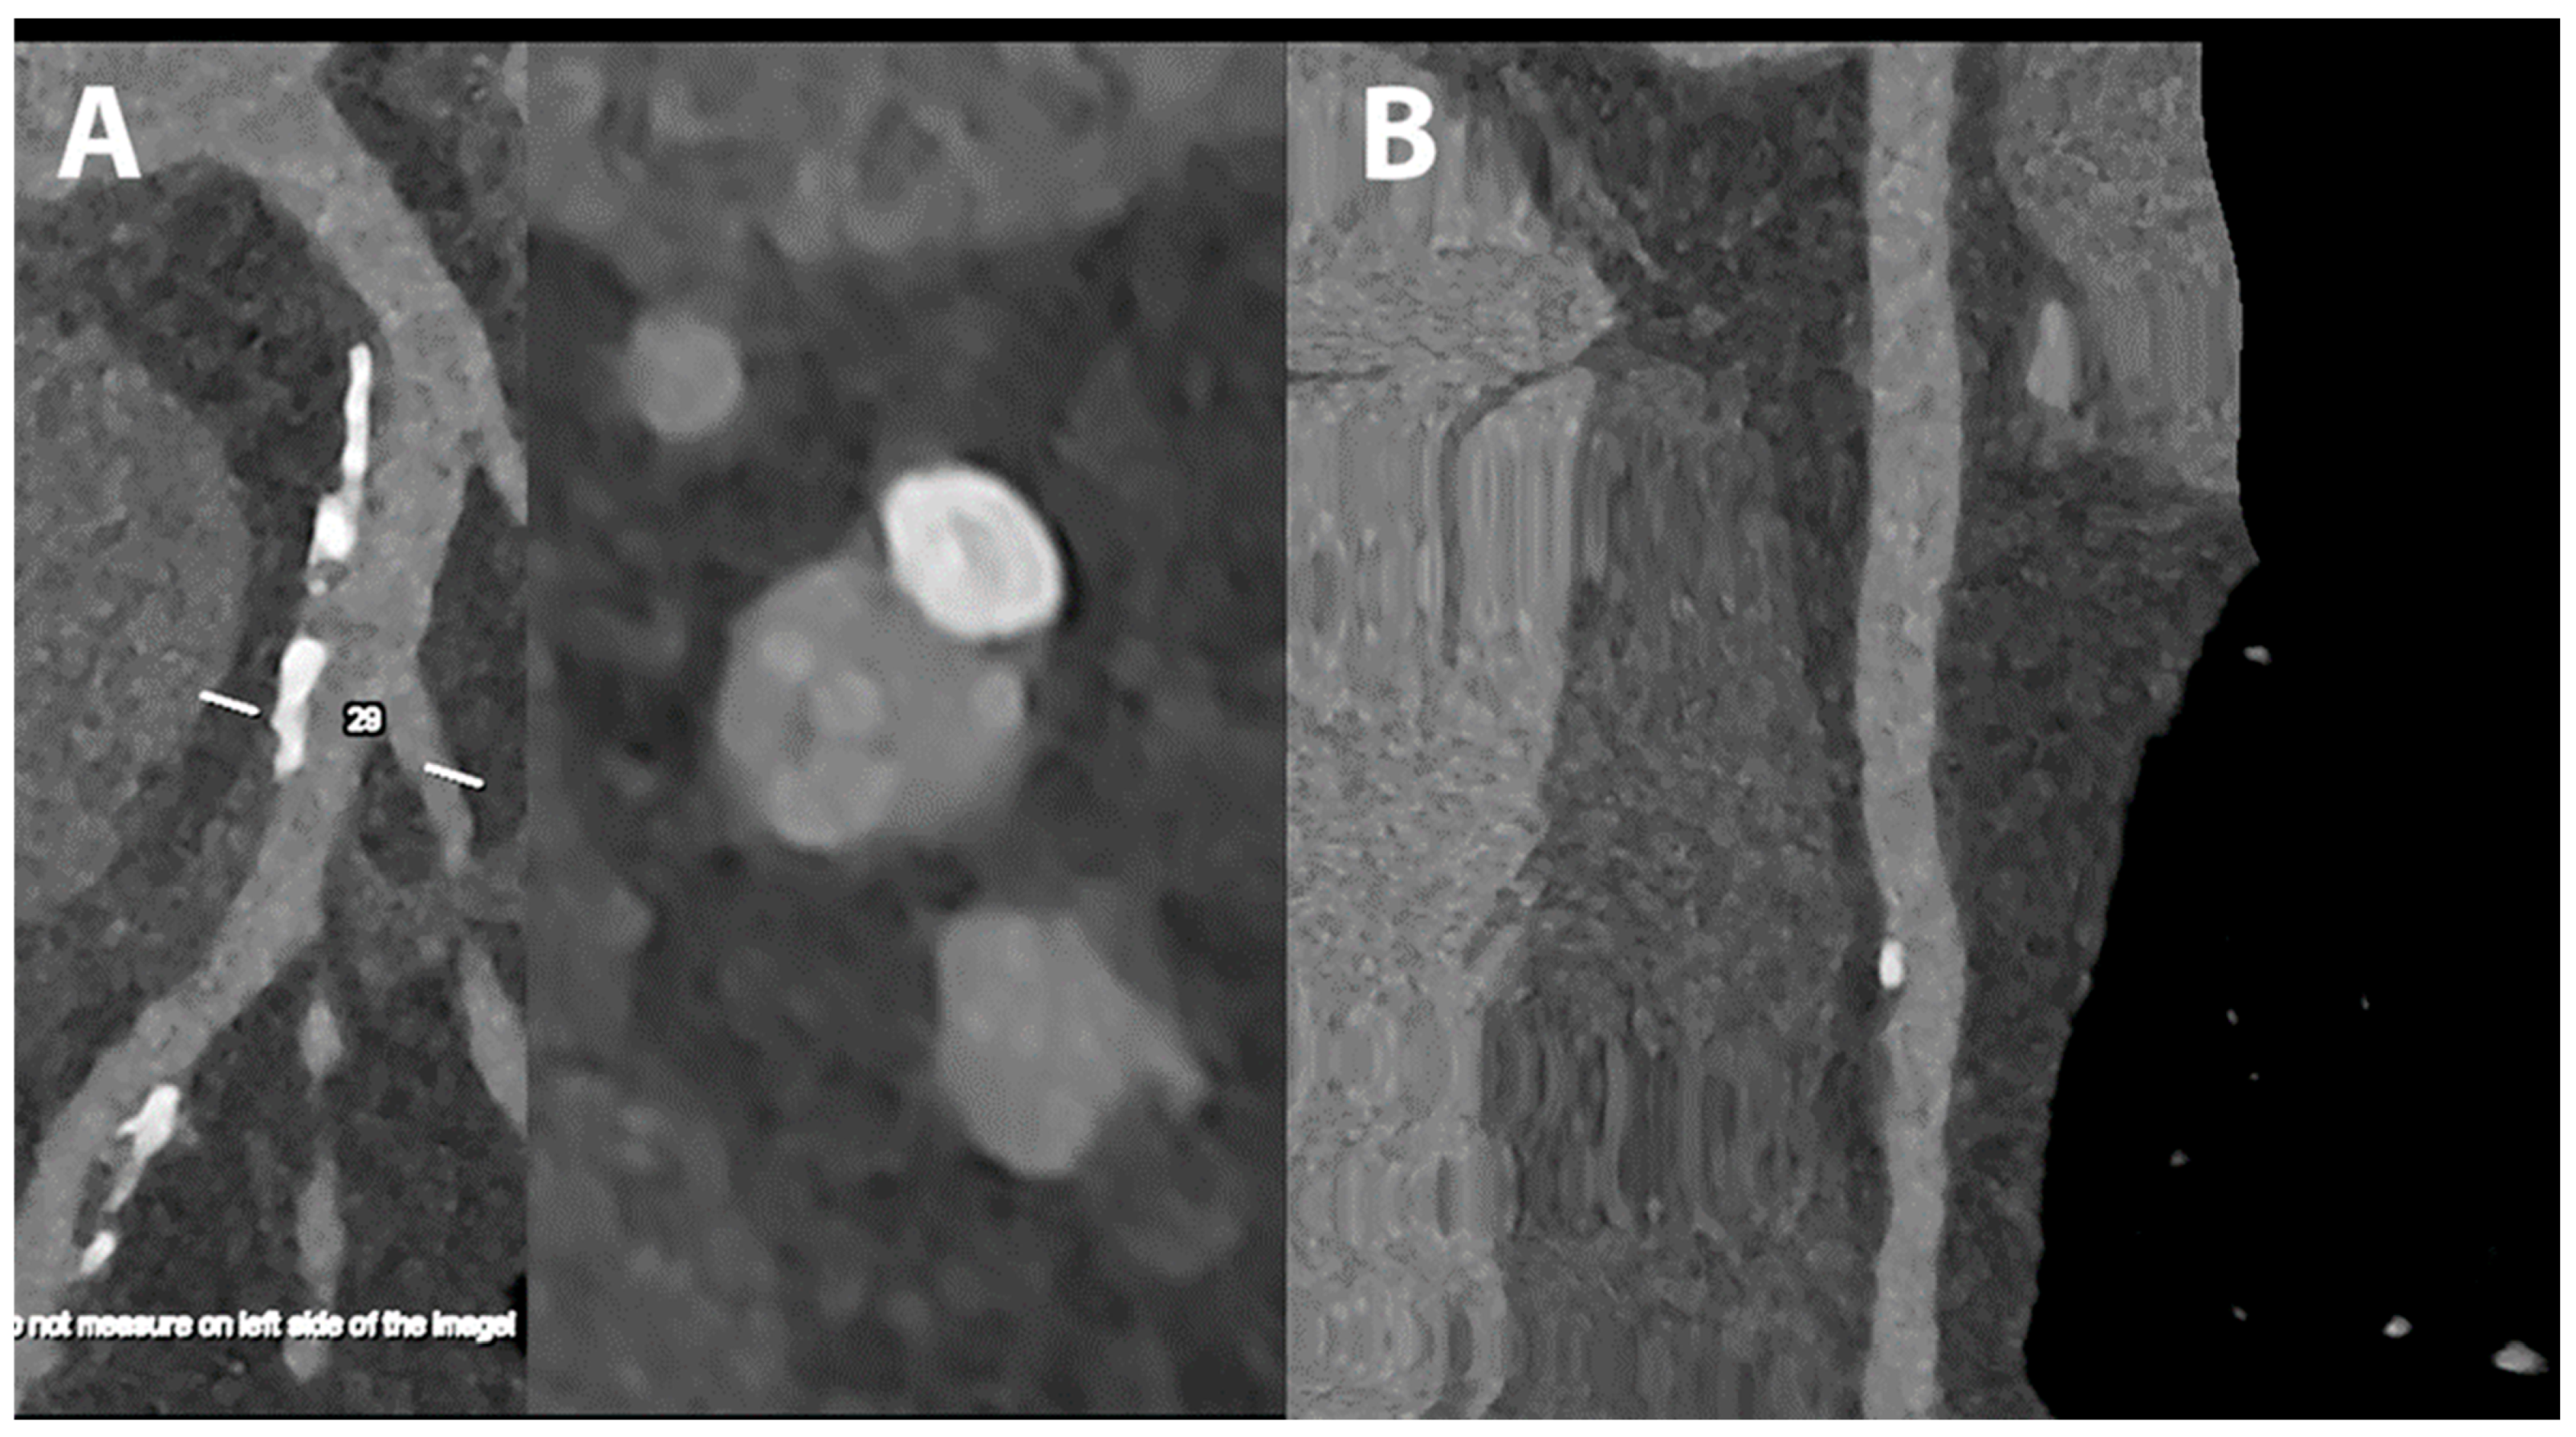

5.4. Coronary Artery Stenting

- Mannil, M.; Hickethier, T.; von Spiczak, J.; Baer, M.; Henning, A.; Hertel, M.; Schmidt, B.; Flohr, T.; Maintz, D.; Alkadhi, H. Photon-Counting CT: High-Resolution Imaging of Coronary Stents. Investig. Radiol. 2018, 53, 143–149. [Google Scholar] [CrossRef]

- Symons, R.; De Bruecker, Y.; Roosen, J.; Van Camp, L.; Cork, T.E.; Kappler, S.; Ulzheimer, S.; Sandfort, V.; Bluemke, D.A.; Pourmorteza, A. Quarter-millimeter spectral coronary stent imaging with photon-counting CT: Initial experience. J. Cardiovasc. Comput. Tomogr. 2018, 12, 509–515. [Google Scholar] [CrossRef] [PubMed]

- von Spiczak, J.; Mannil, M.; Peters, B.; Hickethier, T.; Baer, M.; Henning, A.; Schmidt, B.; Flohr, T.; Manka, R.; Maintz, D.; et al. Photon Counting Computed Tomography With Dedicated Sharp Convolution Kernels: Tapping the Potential of a New Technology for Stent Imaging. Investig. Radiol. 2018, 53, 486–494. [Google Scholar] [CrossRef] [PubMed]

- Boccalini, S.; Si-Mohamed, S.A.; Lacombe, H.; Diaw, A.; Varasteh, M.; Rodesch, P.A.; Villien, M.; Sigovan, M.; Dessouky, R.; Coulon, P.; et al. First In-Human Results of Computed Tomography Angiography for Coronary Stent Assessment With a Spectral Photon Counting Computed Tomography. Investig. Radiol. 2022, 57, 212–221. [Google Scholar] [CrossRef] [PubMed]

- Bratke, G.; Hickethier, T.; Bar-Ness, D.; Bunck, A.C.; Maintz, D.; Pahn, G.; Coulon, P.; Si-Mohamed, S.; Douek, P.; Sigovan, M. Spectral Photon-Counting Computed Tomography for Coronary Stent Imaging: Evaluation of the Potential Clinical Impact for the Delineation of In-Stent Restenosis. Investig. Radiol. 2020, 55, 61–67. [Google Scholar] [CrossRef] [PubMed]